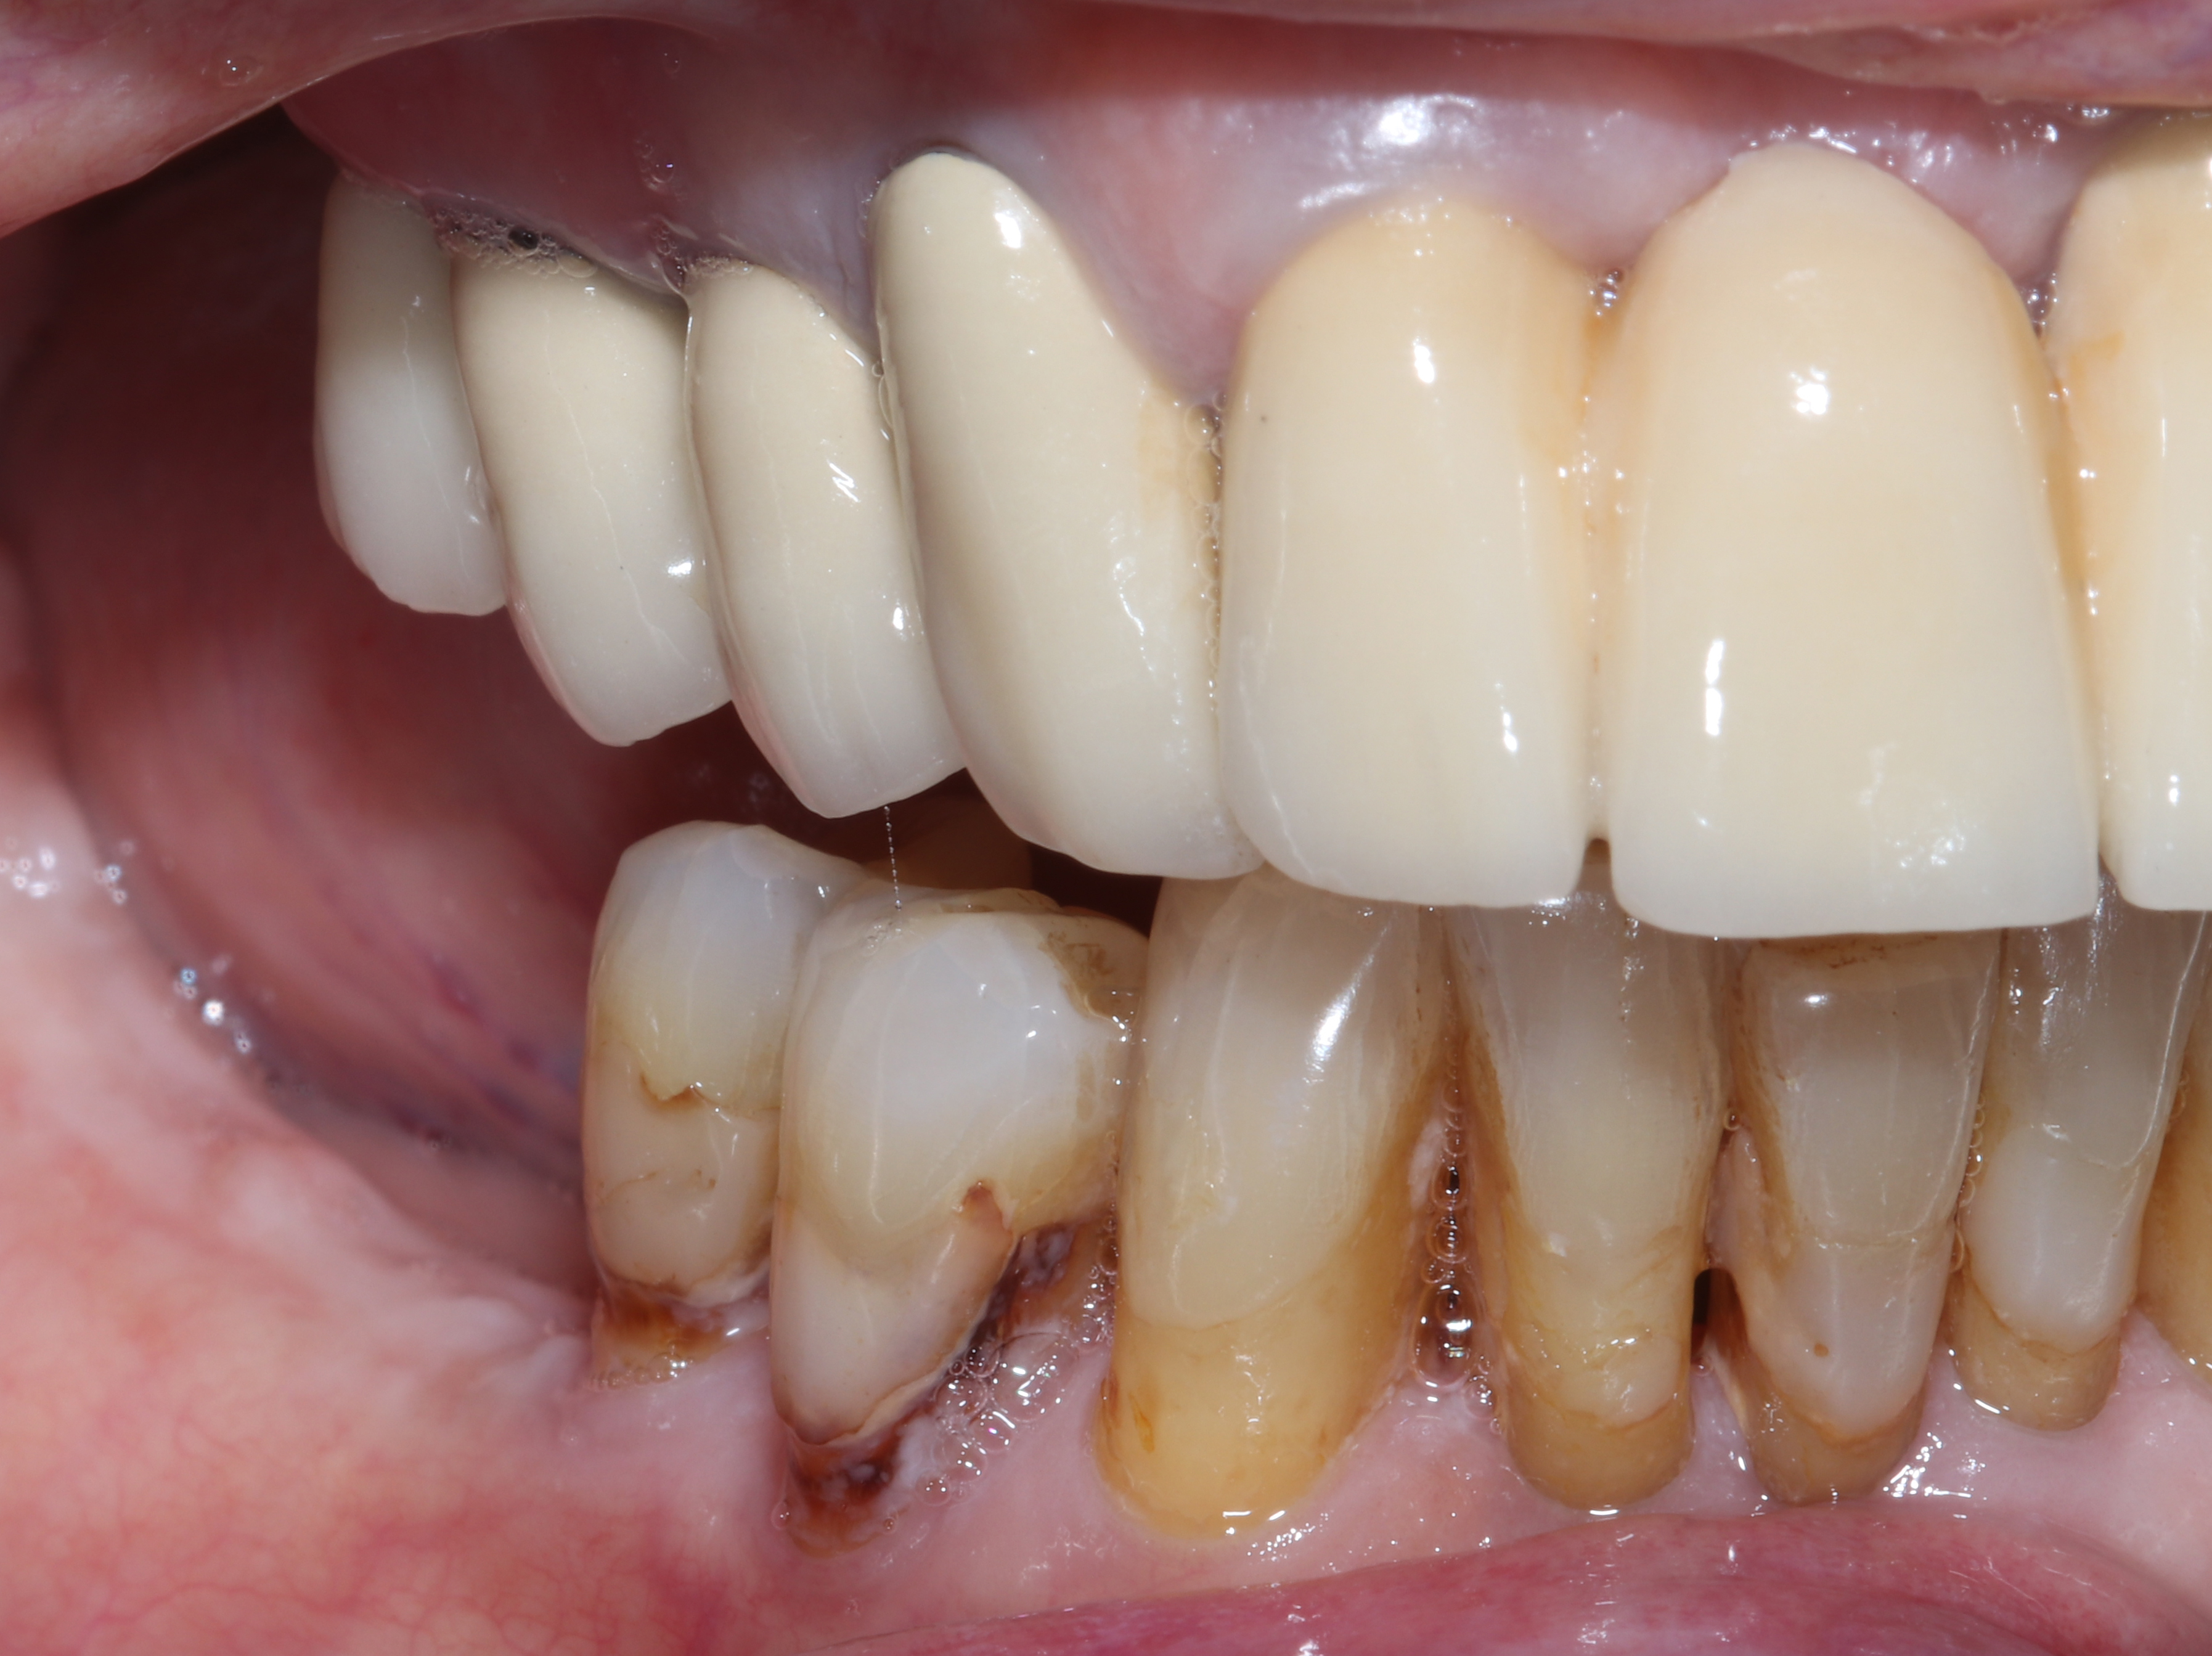

Αρχική κατάσταση - Πλάγια άποψη

Αρχική κατάσταση - Μασητική άποψη

Η κλινική εξέταση έδειξε επαρκή μαλακά μόρια και ικανοποιητικό προσθετικό χώρο με τα δόντια του αντίστοιχου φραγμού. Παρατηρήθηκαν επίσης εκτεταμένες εμφράξεις και τερηδόνες στα δύο δόντια μπροστά από το κενό, γεγονός που οδήγησε στην απόφαση για αποκατάστασή τους με ολόκεραμικες στεφάνες ζιρκονίου.